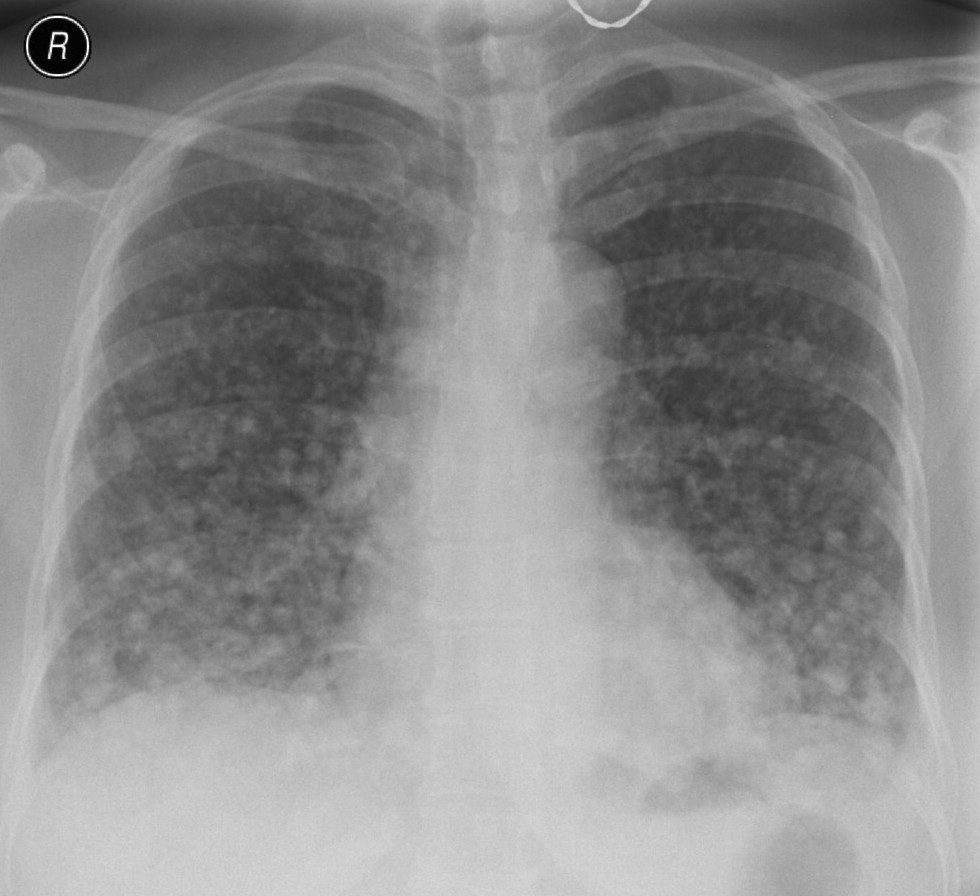

23. Pulmonary metastases, bidirectional (PA and right lateral) plain chest radiograph.

51 year old woman, endometrial carcinoma. Numerous ring shadows bilaterally in basal dominance (max. appr. 12 mm). Left pleural effusion of one finger wide.